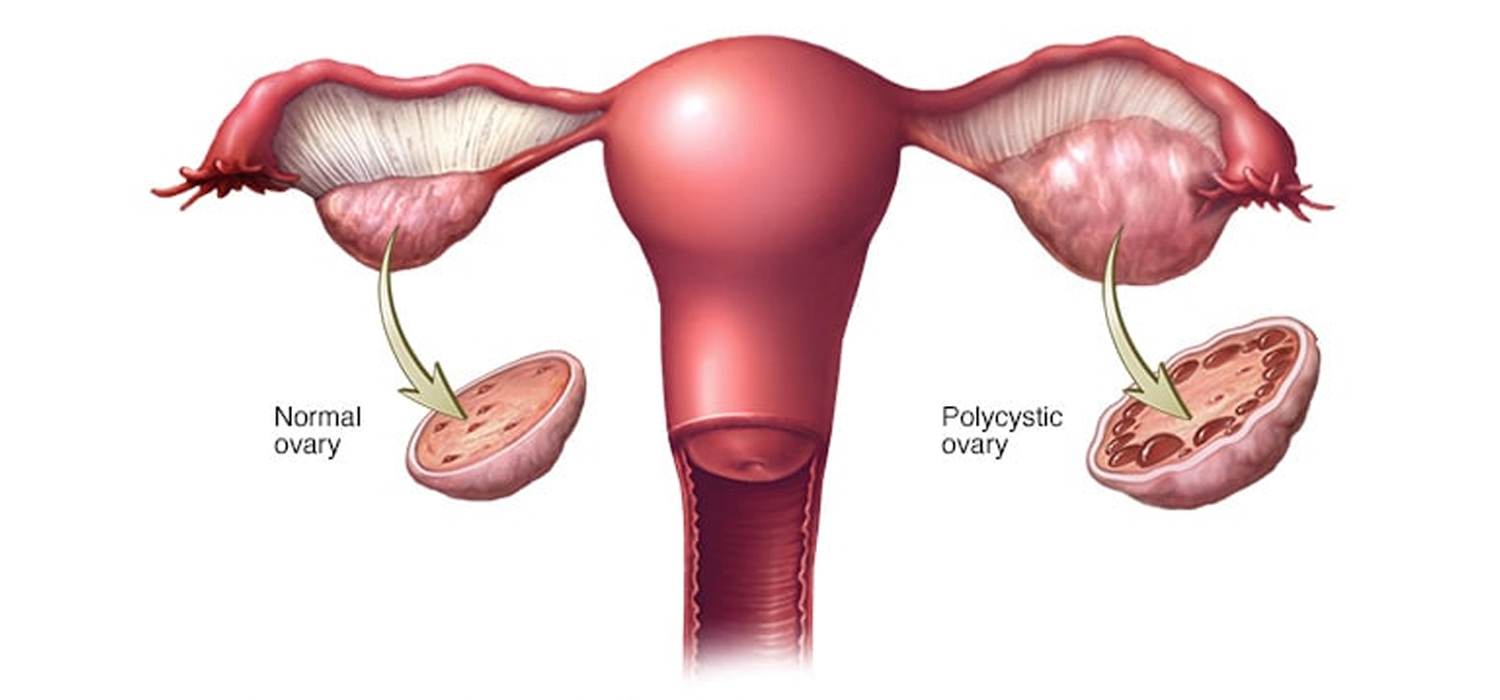

Expert care for PCOD/PCOS, Uterine Cysts/Fibroids, recurring Allergies, and specialized homeopathic guidance for delayed teething in children.

Women & Child Health

Natural care for PCOD/PCOS, Uterine Fibroids, and chronic Allergies. We also provide gentle remedies for Delayed Teething in kids.

PCOD / PCOS / Fibroid

बच्चेदानी में गांठ